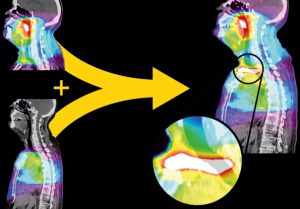

VoxAlign Deformation Engine™

Bu araç, CT-CT hizalama için tasarlanan dünyanın ilk deforme edilebilir hizalama algoritmasıdır. Bu algoritma, görüntülerden daha çok veri toplayarak hizalamanın daha doğru yapılmasını sağlar.

Bu araç, CT-CT hizalama için tasarlanan dünyanın ilk deforme edilebilir hizalama algoritmasıdır. Bu algoritma, görüntülerden daha çok veri toplayarak hizalamanın daha doğru yapılmasını sağlar.

Karşılıklı bilgi yönteminin tersine, bu yoğunluk tabanlı yöntem, CT kontrast ekranının tamamını kullanarak iki tarama görüntüsünü eşler. Ayrıca hizalama için milyonlarca derece özgürlük sağlar, böylece anatomideki hem yerel hem de global değişiklikler dikkate alınır.

Çoğu algoritmanın bu düzeyde doğruluğu sağlaması saatler sürer, bizim aracımız bu işi birkaç saniyede yapmaktadır.

VoxAlign Deformation Engine aracının gücü, MIM’in tüm yenilikçi araçlarında bulunmaktadır.

Doz Akümülasyonu

Herhangi bir sayıda planlar, deforme edilebilir şekilde akümüle edilebilir.

MIM Maestro ve VoxAlign Deformation Engine aracını birlikte kullanarak çoklu dozları kısa sürede deformasyon yapabilirsiniz ve bunları yeni tedavi planlama CT’sine aktararak hastaya verilecek toplam dozu daha iyi görselleştirebilirsiniz.

MIM’in deformasyon özellikleri sayesinde, farklı aylarda yapılmış tarama görüntüleri, deforme edilerek hizalanabilir, böylece doz dağılımı doğru şekilde gösterilir ve tedavi planlama sürecine duyduğunuz güven artar.